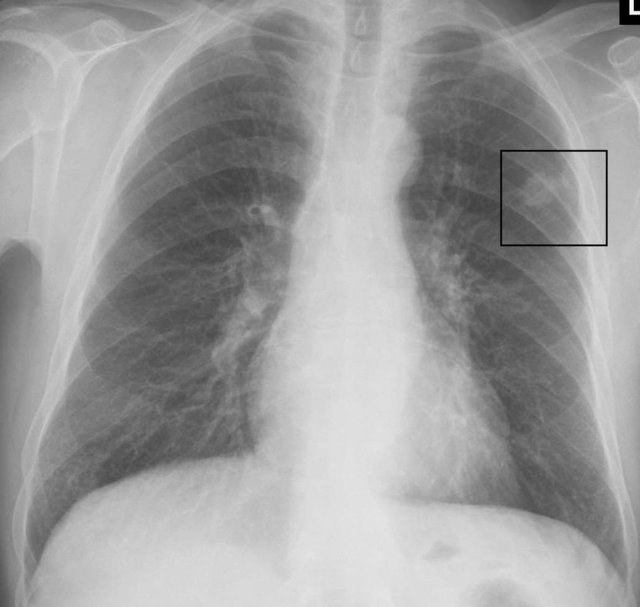

Bildgebung

© wikipedia.org/KGH, CC BY-SA 3.0

• Röntgen-Thorax bzw. CT-Thorax zum Nachweis der Raumforderung,